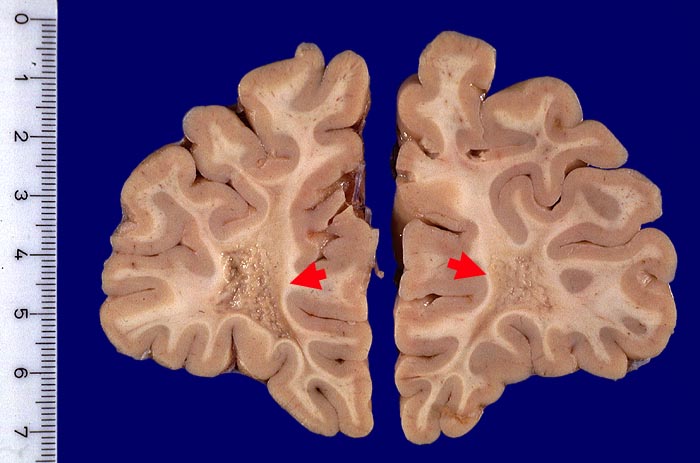

Grau verfärbte und eingesunkene Areale mit granulärer Oberfläche im frontalen Marklager beidseits.

Alte Entmarkungsherde (Dm 1,5cm) der frontoorbitalen Marksubstanz

links und des Balkenknies (Dm 0,5cm): teilweise wiederbemarkte nicht aktive Multiple Sklerose Herde